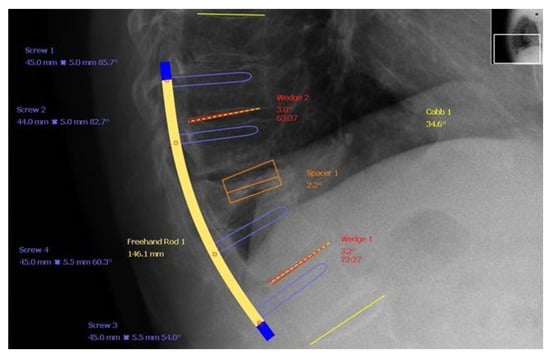

8.2. Surgical Treatment

- (3)